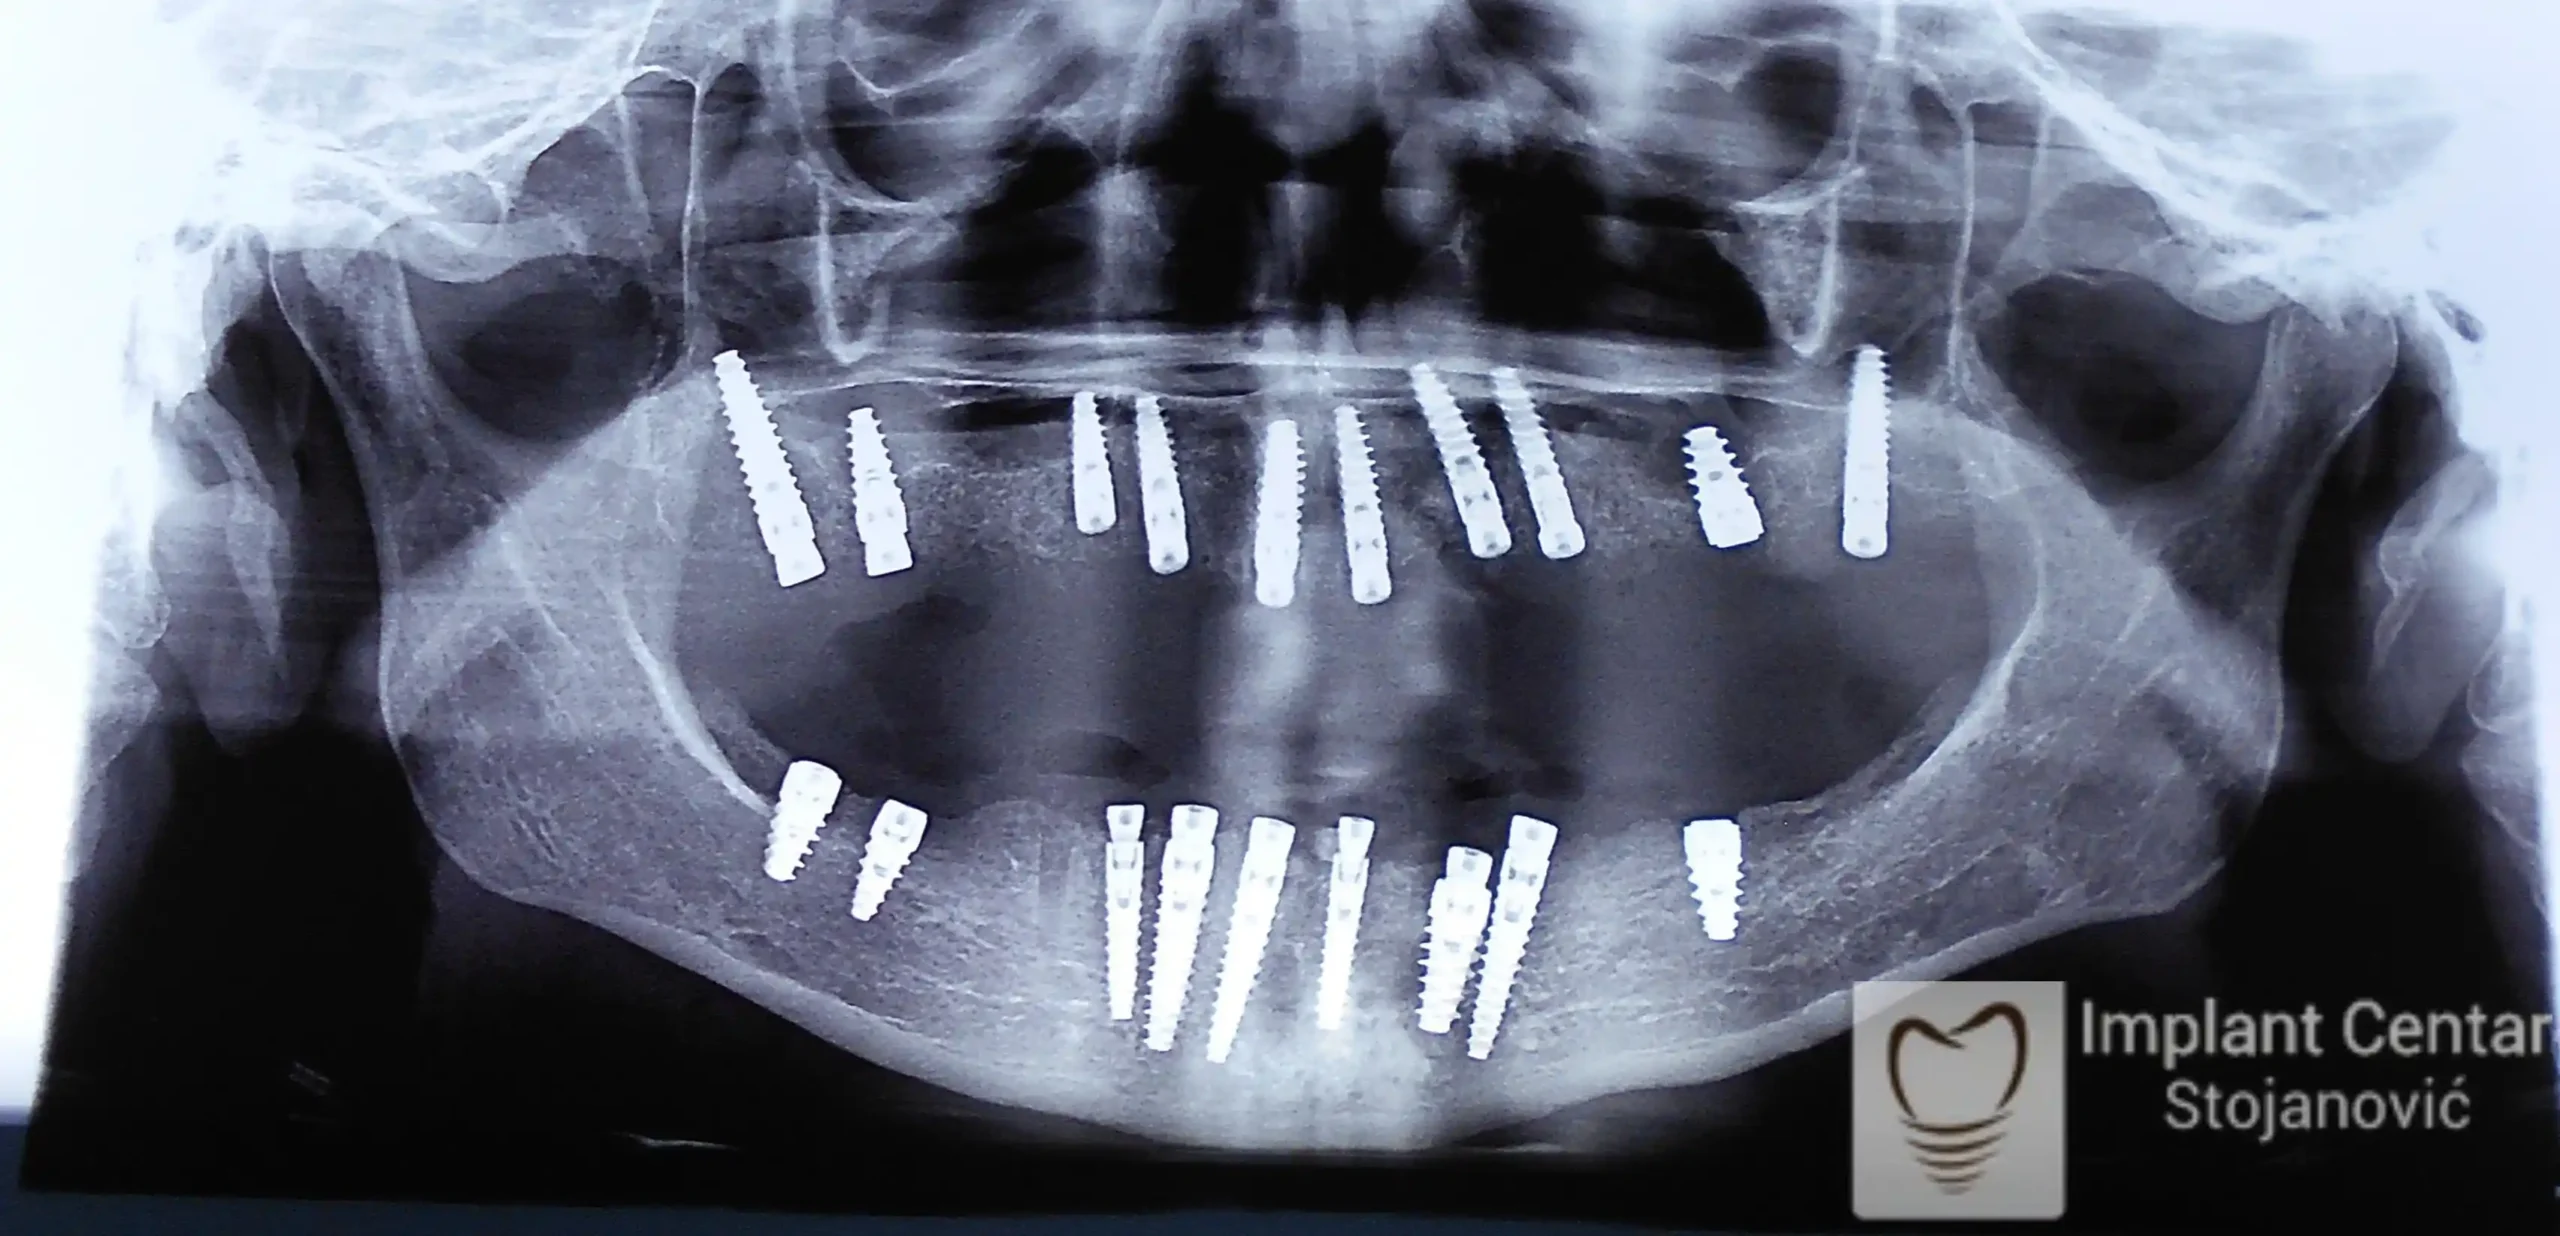

Ugrađeno je deset implantata u gornjoj vilici, u raspoloživu kost uz dodavanje veštačke kosti, od čega su dva tuberopterigoidna implantata. Ovim pristupom izbegnuta je potreba za sinus liftom, a postignuta maksimalna stabilnost.

Veći broj implantata omogućio je ravnomeran prenos žvačnih sila i izuzetnu stabilnost budućeg fiksnog rada.

U donjoj vilici su istovremeno izvađeni svi preostali zubi i ugrađeno je osam implantata.

• Ukupno je u gornjoj vilici ugrađeno 10 implantata kako bi se obezbedilo ravnomerno opterećenje pri žvakanju, a u donjoj vilici 8 implantata, što je omogućilo optimalnu stabilnost.